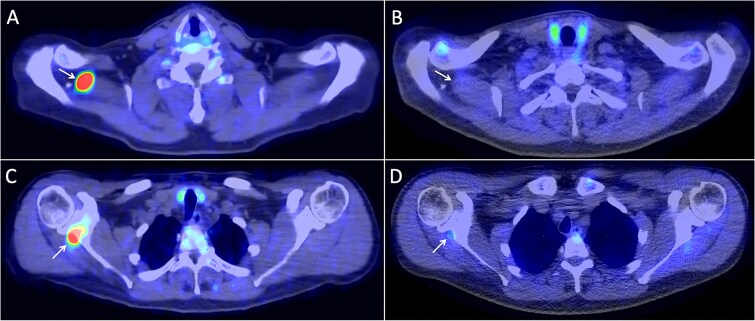

Gallium-68-DOTA-Tyr3-Octreotate (Ga-68-DOTATATE) positron emission tomography/computed tomography (PET/CT) has recently been shown to have utility for the localization of phosphaturic mesenchymal tumors (PMT) that cause tumor-induced osteomalacia (TIO), a rare renal phosphate-wasting disorder. The aim of this study was to evaluate the accuracy of Ga-68-DOTATATE PET/CT in localizing PMTs causing TIO and to compare its performance with other functional imaging modalities. Prospective recruitment and retrospective chart review of 30 patients with suspected TIO and evaluation with Ga-68-DOTATATE PET/CT between 2017 and 2023 were conducted at a tertiary medical center. True positive (TP) lesions were defined by histological confirmation of PMT. There were 22 TP lesions identified among 18 patients, with a mean SUVmax of 16.8 (±10.9). Sensitivity, specificity, and accuracy of Ga-68-DOTATATE PET/CT were 85.7%, 77.8%, and 83.3% on patient-based analysis, and 84.6%, 56.3%, and 73.8% on lesion-based analysis. Lesions such as subacute fractures, parathyroid adenomas, thymus uptake, vertebral hemangiomas, bone enchondromas, liver hemangiomas, and avascular necrosis were some of the pitfalls in interpretation. Ga-68-DOTATATE PET/CT led to a significant impact on clinical management in 24 (80%) of patients. The presence of DOTATATE-avid fractures was significantly associated with a localizing scan on univariable (OR 15.0, 95% CI 2.80-110, p = .001) and multivariable analysis (OR 9.45, 95% CI 1.33-98.4, p = .003). Ga-68-DOTATATE PET/CT has good accuracy for the localization of TIO, with superior sensitivity compared to F-18-FDG PET/CT. This significantly impacted clinical treatment decisions. Although DOTATATE-avid fractures may be a source of false positives, they may also indicate a higher probability of a localizing study.